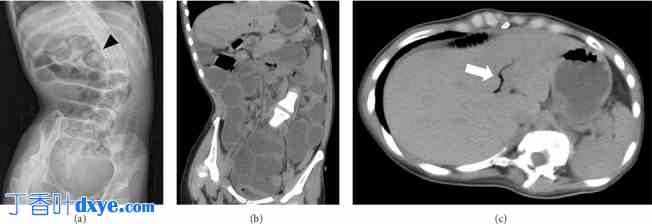

入院时体格检查发现腹胀,但无腹部僵硬、腹部肌紧张和反跳痛等急腹症体征。血液检查结果显示白细胞增多(12,850 个细胞/μL),C 反应蛋白水平略有升高(0.53 mg/dL)。化学检查正常,但 γ-GTP(67 U/L)和总胆固醇(229 mg/dL)略有升高。入院时总胆固醇水平略有升高,很可能是餐后效应,因为高值在入院后并未持续。腹部X光片显示小肠明显扩张(图1(a))。由于患者曾接受过开腹手术并进行过胃造口术,因此作者考虑胃肠炎或粘连性肠梗阻。患者接受了禁食和静脉补液治疗,但病情未见好转。入院后第四天,因怀疑存在小肠梗阻,患者接受了腹部计算机断层扫描(CT)检查。CT结果显示小肠梗阻和胆道积气(图1(b)和1(c)),但未发现肠内肿块。虽然对于没有胆道系统手术史的患者,如果出现胆道积气,应怀疑胆肠瘘,但目前梗阻的原因尚不清楚。

图1

胆石性肠梗阻患者的腹部X线平片和CT扫描结果。腹部X光片显示小肠扩张(a)。箭头指示胃造口钮。冠状位(b)和轴向(c)CT图像分别显示小肠梗阻和胆道气肿(箭头)。